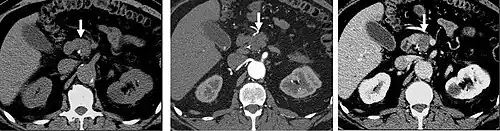

FIGURE 7. Selected images from a renal mass specific protocol CT. Corticomedullary phase (axial 7a) demonstrates peripheral enhancement of the renal cortex with minimal opacification of the renal medulla. There is a large renal cell carcinoma in the left kidney (right in image) which can be differentiated from the normal renal parenchyma by the heterogeneous and differential enhancement. The renal artery and vein are opacified in this phase as well. The collecting system is not opacified (coronal reformat 7b). In the parenchymal phase, the renal cortex and the medulla are enhancing. The renal cell carcinoma in the left kidney is not as well defined when compared to the corticomedullary phase images, but is actually slightly more conspicuous. There is some contrast noted within the collecting system during this phase (7c).